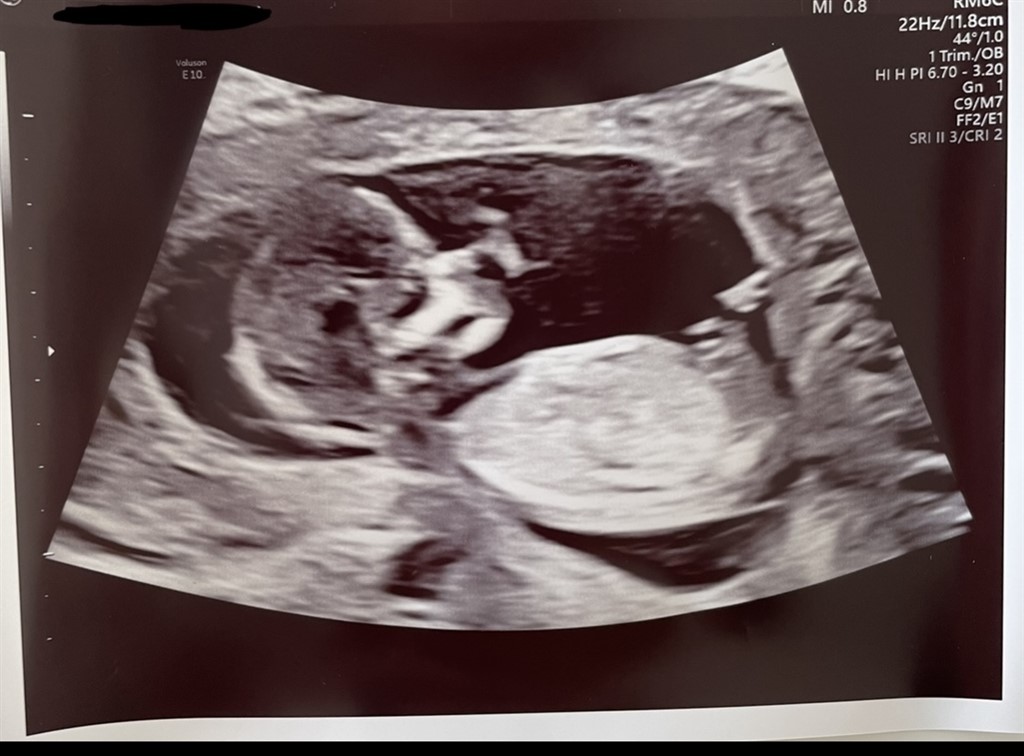

har været til vellykket NF scanning idag og 13+0  Jeg er så nysgerrig på køn, kan nærmest ikke vente de halvanden uge på en kønsscanning.

Er der nogen som er stærke i nub for jeg kan intet tyde ?

Vedhæftede fotos (klik for at se i fuld størrelse)

Næsten 100 procent sikker på det er en dreng

Jeg vil uden tvivl sige en pige.

Jeg vil heller ikke turde gætte på kønnet, synes ikke helt at nubben er så tydelig

Nå.. til vores store overraskelse venter vi os en lille aktiv dreng